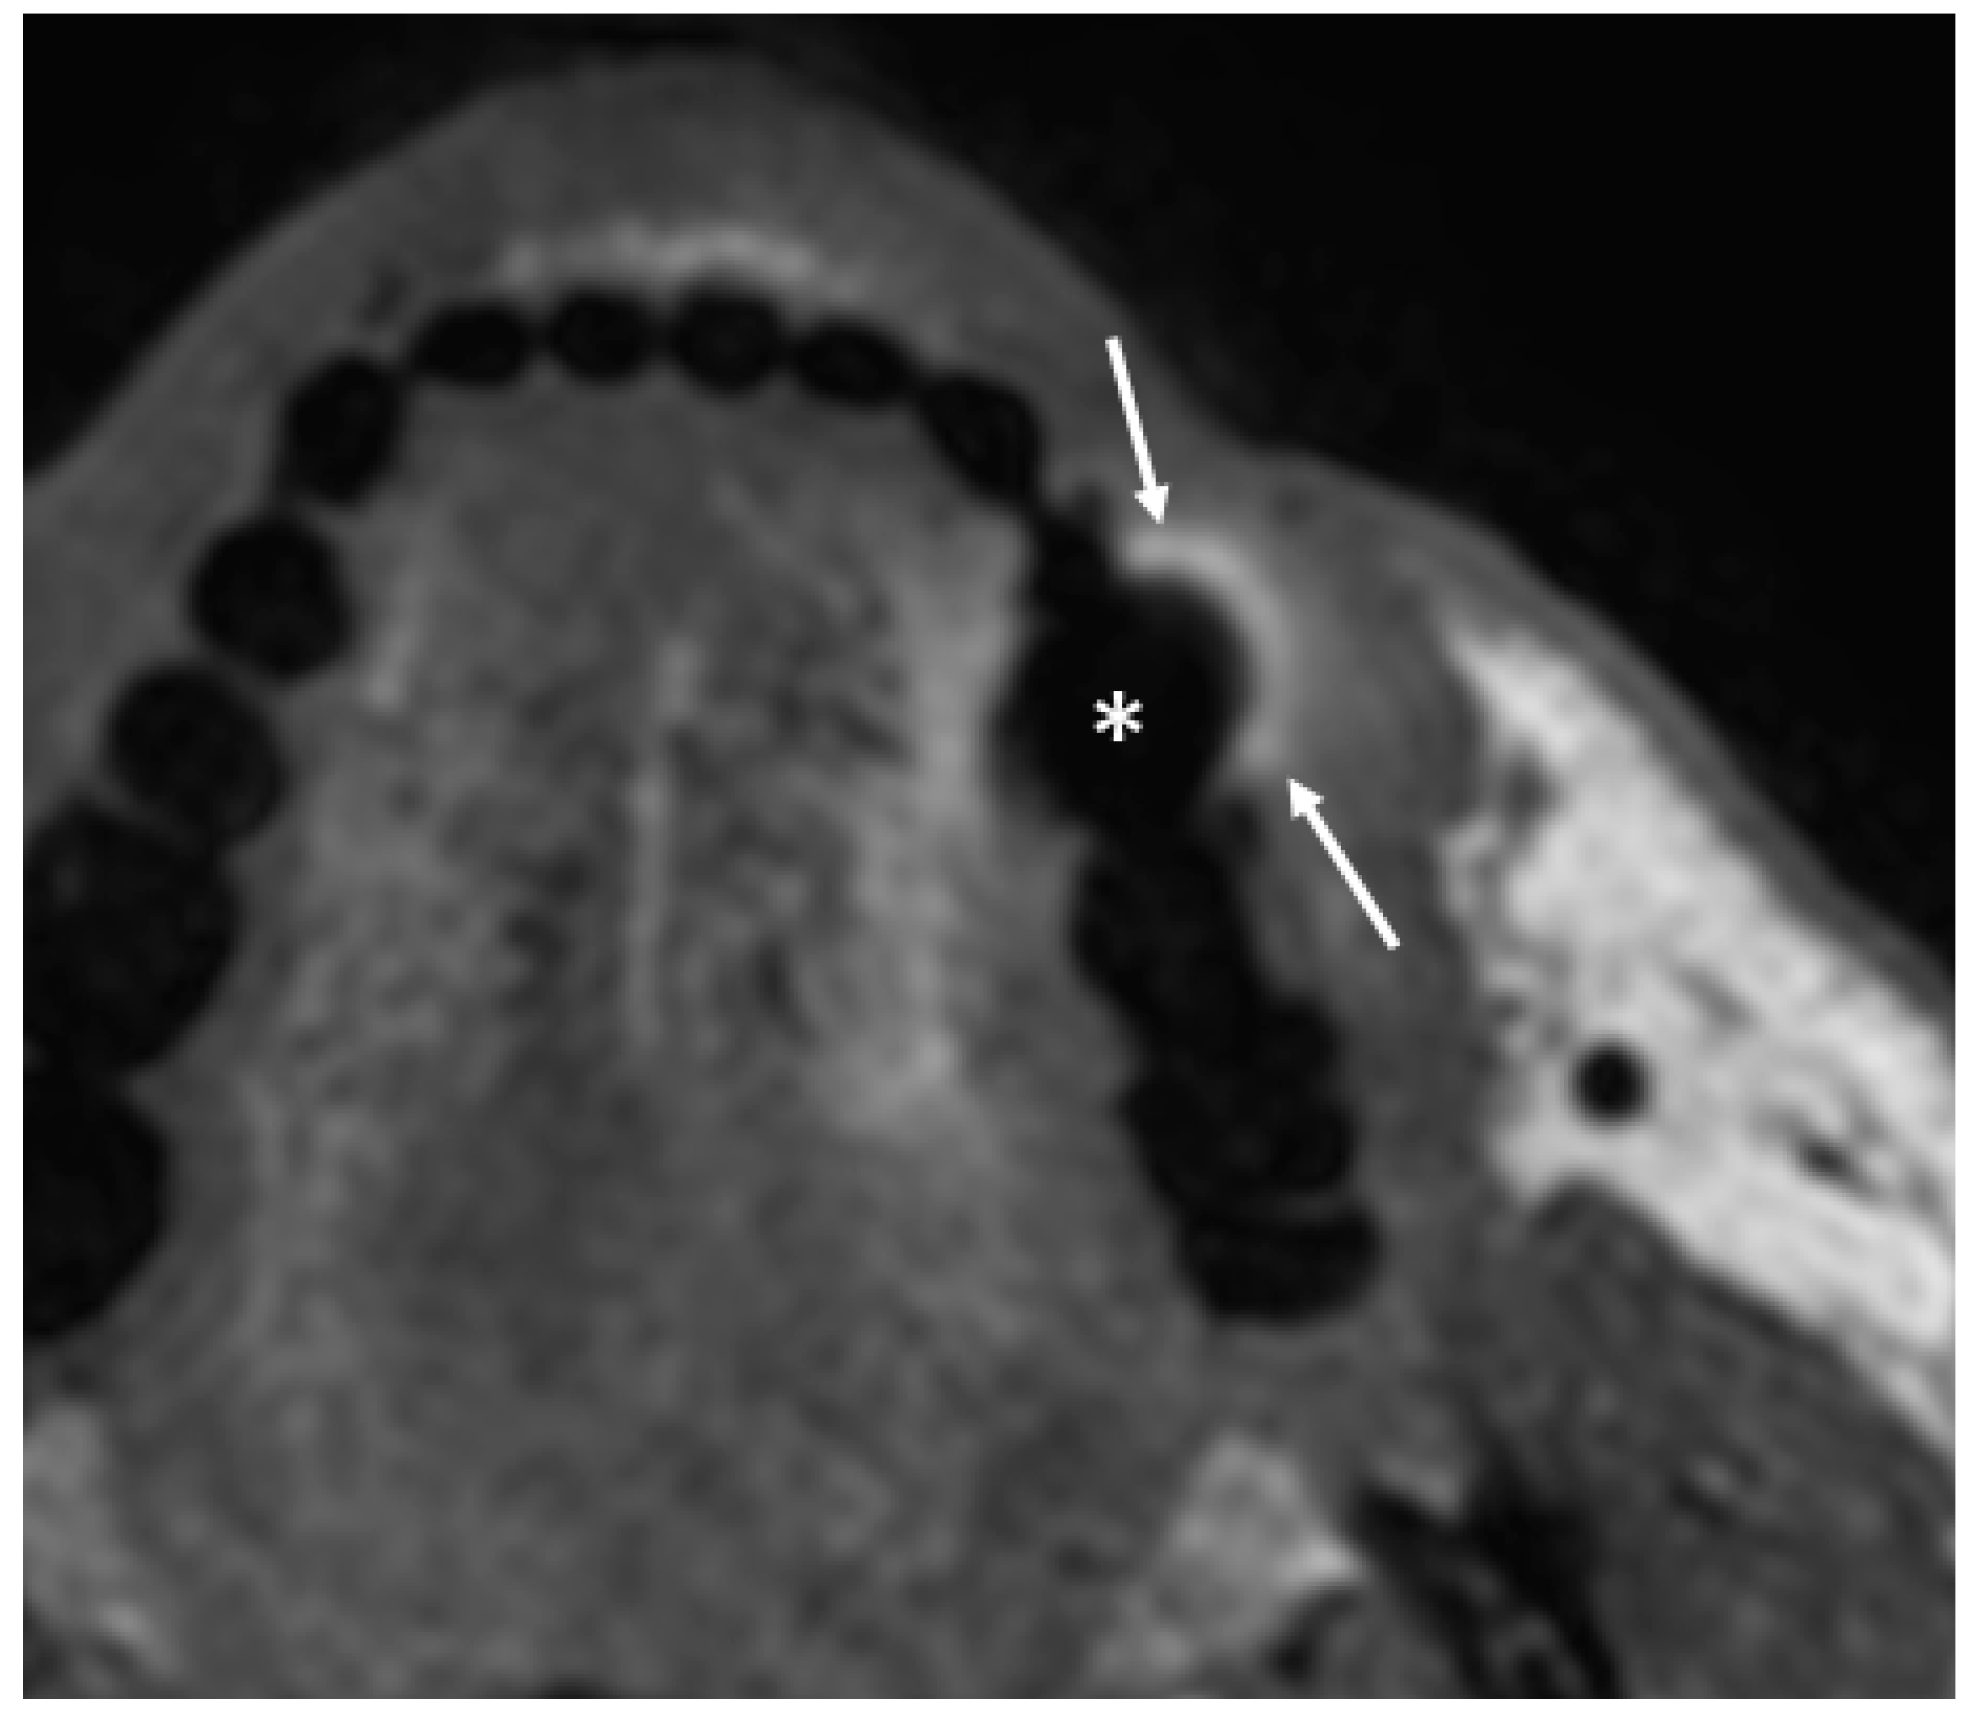

- Puffed cheek technique. The vestibule of the mouth is a virtual cavity due to the contact between the mucosa of the lip, cheek, and gingiva. Puffed cheek technique helps to determine if the lesion is arising from the buccal, gingival, or lingual mucosal surface since patients blow uniformly through pursed lips and the mucosal surfaces appear separated from each other. Therefore, the vestibular cavity can be appreciated as an air-filled horse-shoe-shaped space both on MSCT and MRI (Figure 10 and Figure 11).

- Open mouth technique. Patients open their mouth and the acquisition is obtained with quiet respiration. A device (i.e., a 50 mL syringe) can be used between teeth to ensure the maintenance of the right position [28]. It allows the separation of the palatal mucosa from the muscular component of the tongue clarifying the exact origin, infiltration, and thickness of tumoural masses (Figure 12 and Figure 13).